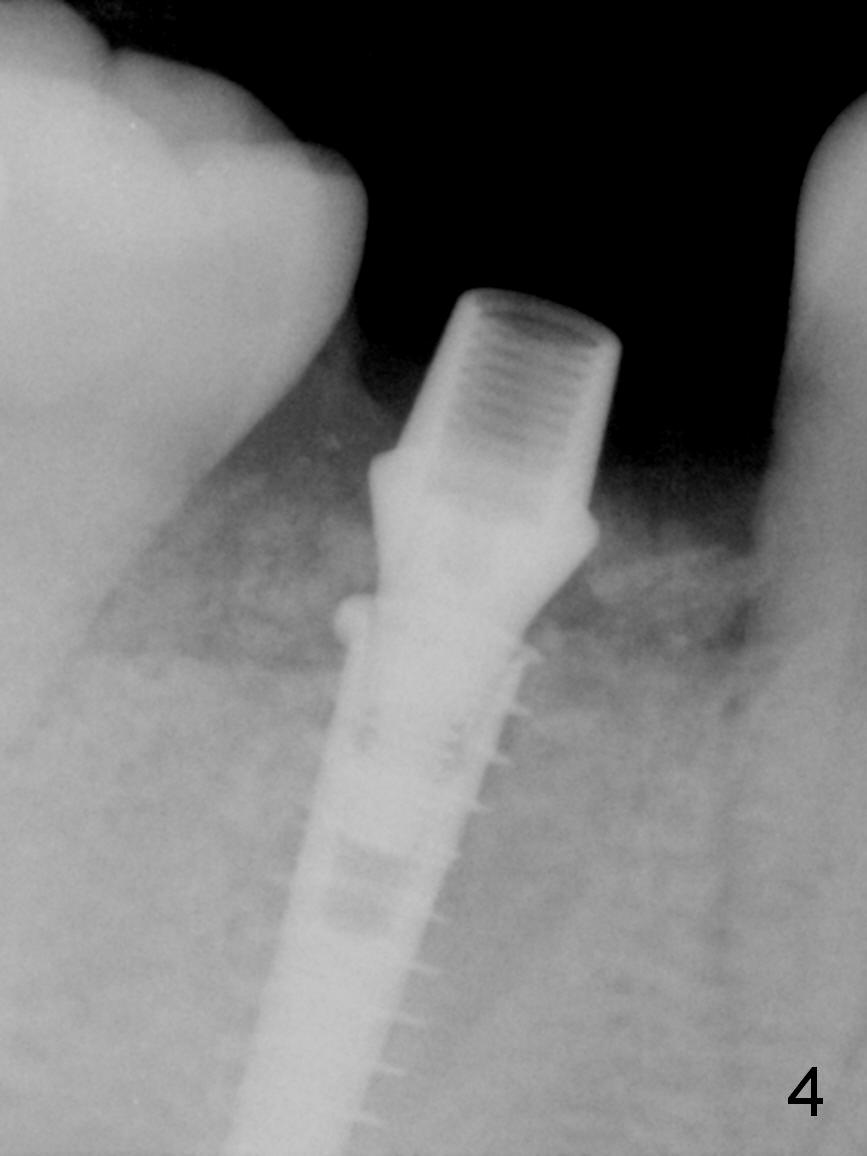

After cleaning the root surface with a surgical curette, a 1.6 mm pilot drill is used to start osteotomy (O) between the mesial (M) and distal (D) roots, followed by a marking bur and 3.8 mm Magic drill 13 mm deep (Fig.1,2). Following root removal, the 3.8 mm drill is reused for 11 mm (Fig.3). After deepening the osteotomy for another 2 mm, a 4.5x13 mm implant is placed with insertion torque of 50 Ncm, followed by allograft (*, .5-2 mm) and a 5x4(2) mm abutment (Fig.4,5). An immediate provisional is fabricated to close the socket (Fig.6 P (lock in)). The detached buccal gingiva (Fig.6 *) is kept in place by applying periodontal dressing (Fig.7 *). Red dashed lines in Fig.1, 3, 5 represents the superior border of the Inferior Alveolar Canal and Mental Foramen.